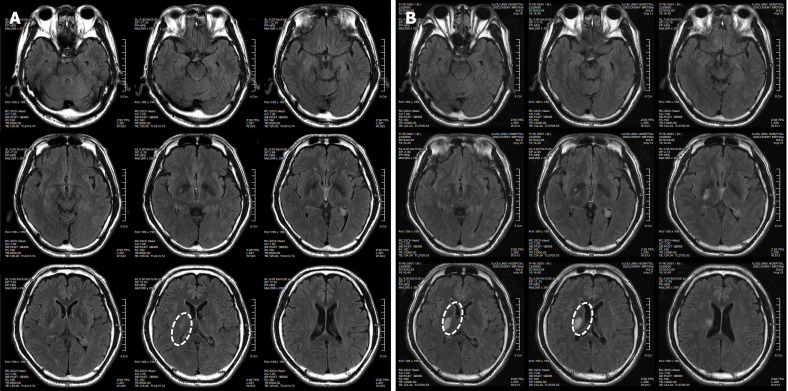

患者于2018年2月17日至18日出現(xiàn)暫時性無力癥狀,早上醒來后突發(fā)急性中風(fēng),導(dǎo)致左上肢和下肢癱瘓?;颊咴诖髮W(xué)醫(yī)院急診室被診斷為Rt紋狀體囊性梗死(圖1A)。他于2018年3月2日出院,僅接受了阿司匹林處方,因為根據(jù)腦計算機(jī)斷層掃描 (CT) 掃描,他的腦血管正常,盡管他的病情在住院期間惡化(圖1)。出院當(dāng)天,他被送往康復(fù)??漆t(yī)院接受長期康復(fù)治療。然后他于2018年3月13日來韓國首爾生物美容與健康公司 (bBHC)-干細(xì)胞治療與研究所 (STRI)接受干細(xì)胞治療。

圖1:微創(chuàng)人臍帶間充質(zhì)干細(xì)胞移植前患者的腦部計算機(jī)斷層掃描圖像。

患者在干細(xì)胞移植后約30個月拍攝腦部CT圖像以確認(rèn)病灶的大小。病灶縮小至0.6cm×0.3cm(圖4)。

圖4:微創(chuàng)人臍帶間充質(zhì)干細(xì)胞移植后患者的腦部計算機(jī)斷層掃描圖像。